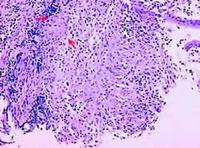

(4)炎症增殖型(瀰漫浸潤型):病變常累及胃壁各層,故胃壁增厚,黏膜呈息肉樣增生。3.組織形態病理病變附近的淋巴結常有腫大及乾酪樣壞死。病理組織學檢查可見典型的乾酪樣肉芽腫,常位於黏膜和黏膜下層,很少累及肌層。組織切片抗酸染色可發現抗酸桿菌。

5.胃鏡活檢切片抗酸染色陽性,有乾酪樣肉芽腫。

2.胃鏡檢查為診斷胃結核的主要方法。胃鏡下肉眼觀察胃結核病變仍不易與胃潰瘍或胃癌等鑑別。但活組織檢查發現下列情況則有助於結核的診斷:①乾酪樣肉芽腫;②切片抗酸染色或活檢材料培養發現結核桿菌;③聚合酶鏈反應(PCR)檢測,結核桿菌DNA呈陽性。若病變位於肌層而未破壞黏膜,胃鏡檢查時易誤診為平滑肌腫瘤。對黏膜下層病變,如活檢時取材過淺亦可呈陰性。